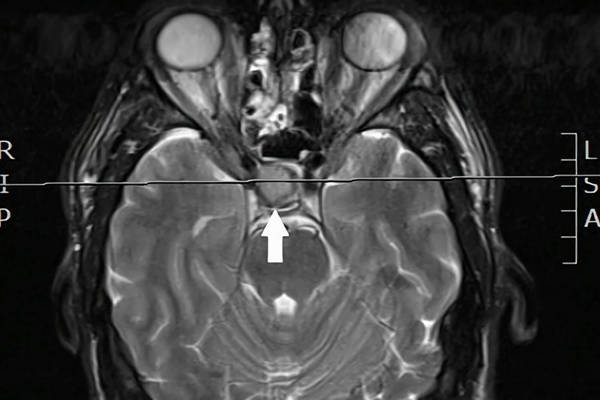

Photophobia: an unusual symptom of a pituitary macroadenoma